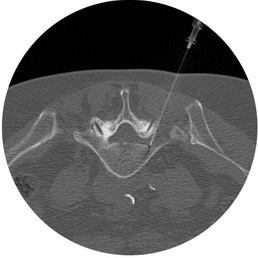

CT-Bild Lagekontrolle der PRT-Nadel

Mit der Computer-Tomographie ist es möglich, die Schmerzursache wie eine komprimierte Nervenwurzel oder Narbenbildung nach Bandscheibenoperation oder degenerativ veränderte Wirbelgelenke sichtbar zu machen und die Medikamente genau an diese Stelle einzuspritzen. Dies geschieht mit einer sehr dünnen Nadel, die unter Bildkontrolle bis zu der gewünschten Stelle vorgeschoben wird. Dieses Vorgehen ermöglicht neben der präzisen und korrekten Platzierung der Medikamente auch eine gefahrlose Durchführung des Eingriffes bei geringstem Risiko einer unbeabsichtigten Verletzung benachbarter Strukturen. Durch die Verwendung einer kleinen Nadel ist der Eingriff hinsichtlich seiner Invasivität mit einer tiefen Schmerzspritze vergleichbar. Komplikationen der computertomographisch geführten Schmerztherapie sind selten, allerdings ist an der Hals- und Brustwirbelsäule wegen der anatomischen Gegebenheiten das Risiko von Komplikationen etwas höher.